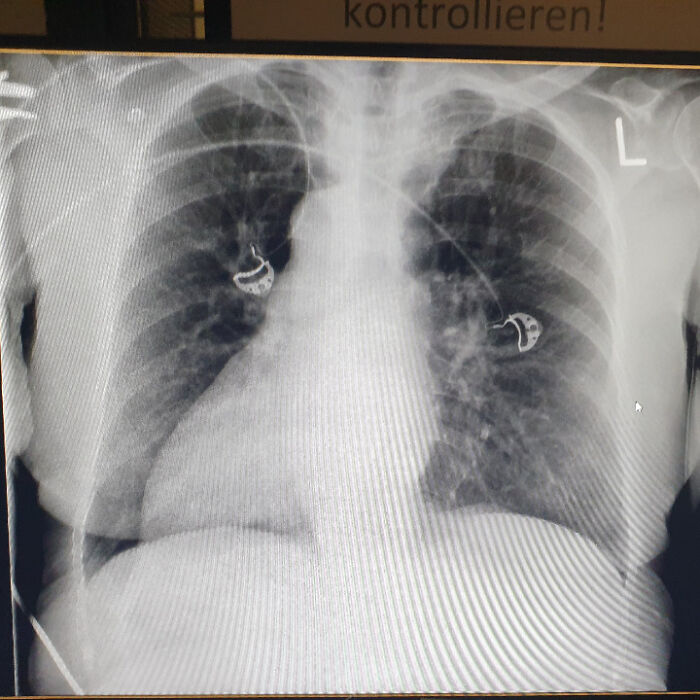

#32

Maybe not so relevant, but when they made a full body x-ray of my grandmoms identical twin sister, not only did it turn out all her organs were mirrored (her heart was on the right side etc) but she also had 4 kidneys… woman was 60+ at the time and they never knew before.

Image source: Sanvi